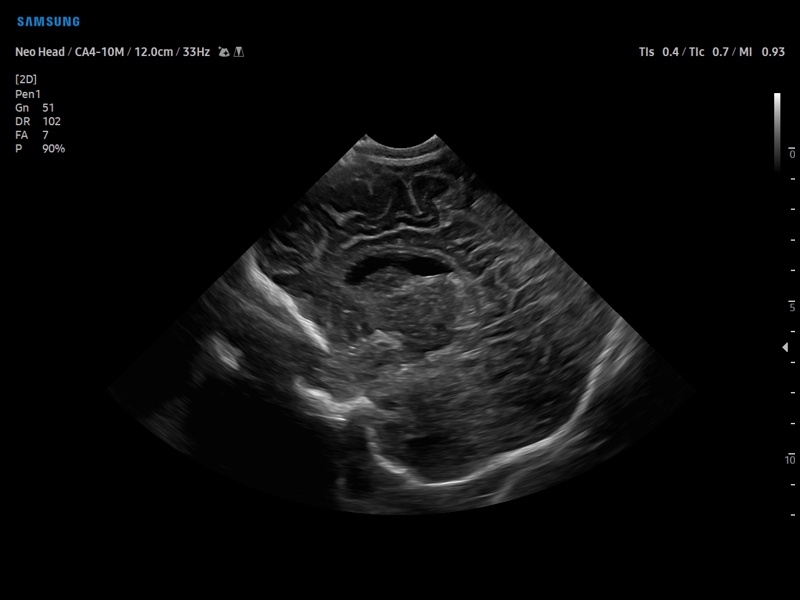

• Педиатрия и неонатология

• M - одномерный режим для исследования сердца, анатомический М-режим (необходим кардиопакет), CM - цветной М-режим (необходим кардиопакет).

• Модуль5D CNS– программа автоматического построения основных срезов головного мозга плода в режиме объемного сканирования.